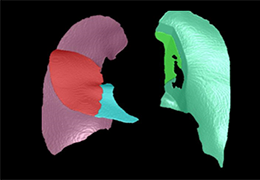

Segmentation

Segmentation of tissue (e.g., isolating the brain, differentiating gray and white matter) is performed using region-growing methods, filter operations as well as the application of 3D templates. Using the mouse it is very easy to explore a 3D volume with superimposed pseudocolor-coded statistical maps in a four-window representation showing a sagittal, coronal, transversal and oblique section. Based on a (segmented) 3D data set a three-dimensional reconstruction of the subjects' head and brain can be calculated and displayed from any specified viewpoint using volume or surface rendering.

Advanced segmentation tool means even higher quality segmentation of grey and white matter and boundaries.

The surface reconstruction procedure starts with a sphere (recursively tesselated icosahedron) or a rectangle, which slowly wraps around a (segmented) volume data set. In order to avoid topological defects and to let the surface smoothly grow into deep sulci, a dynamic mesh algorithm was developed which automatically invents new polygons on the fly at places where they are needed. A reconstructed cortical surface may be inflated, cut interactively and slowly unfolded minimizing areal distortions. Statistical 3D maps may be superimposed on reconstructed, inflated or flattened cortex. Signal time courses may be invoked by simply pointing to any region of a visualized surface.